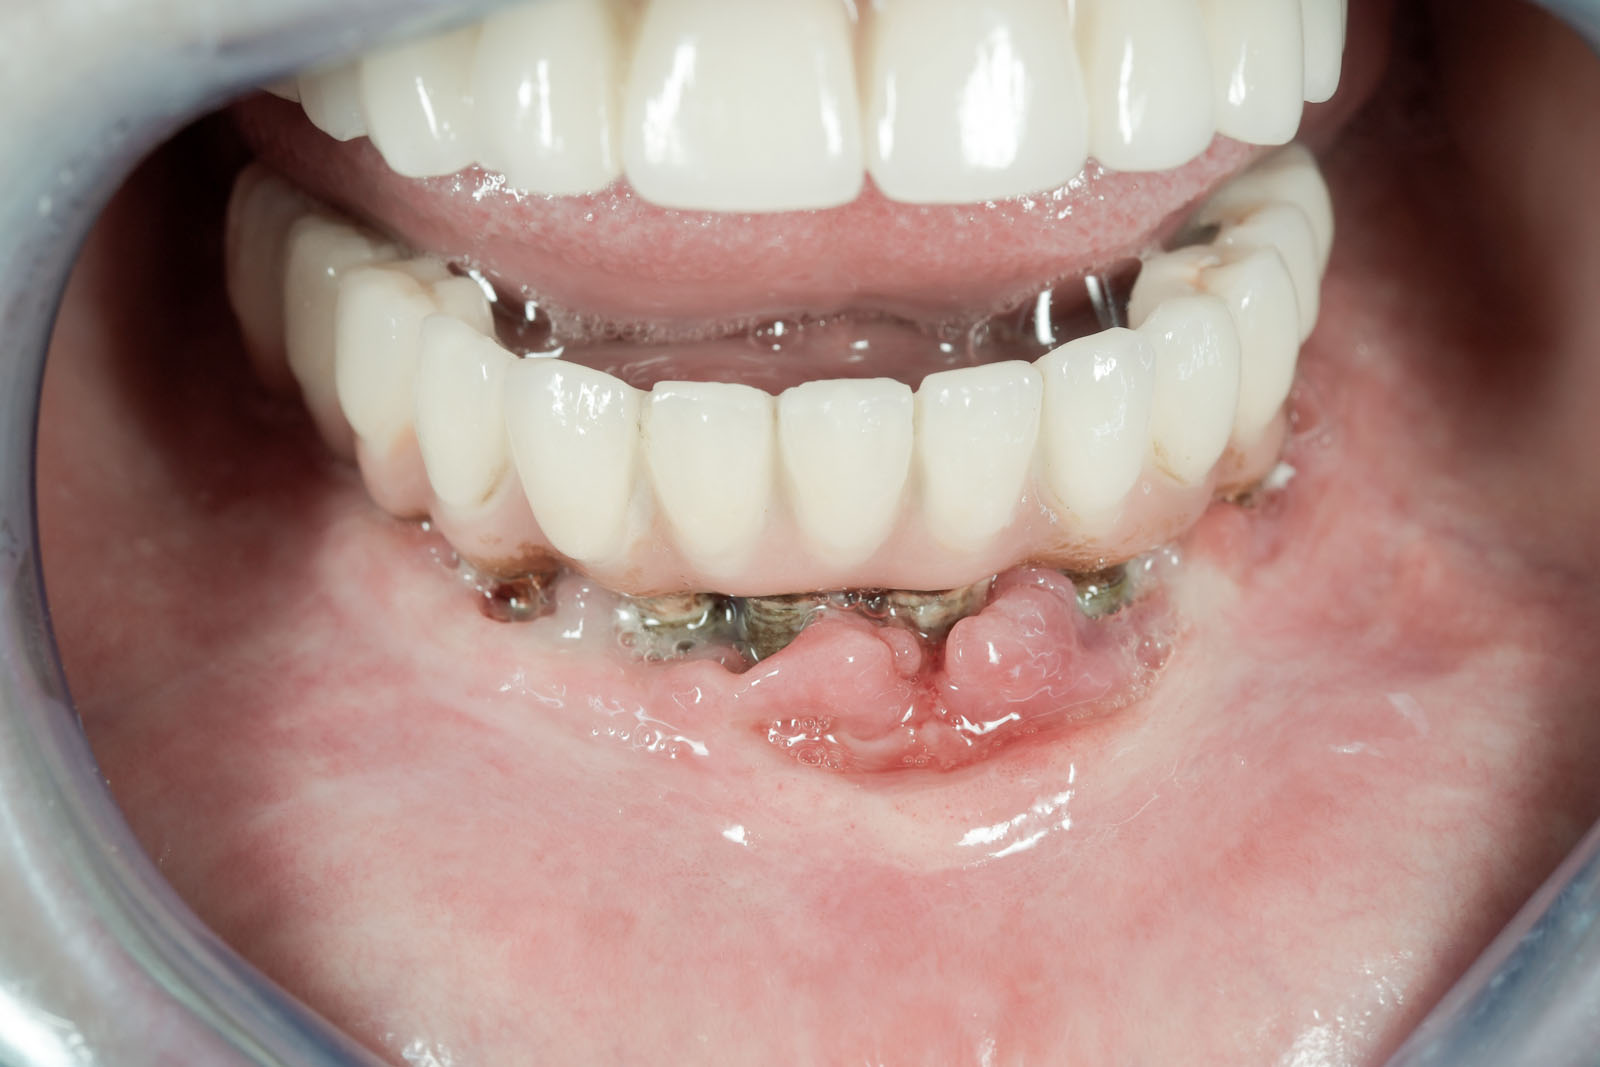

Zabiegi profilaktyczne są bezwzględnym wymogiem przed planowanym leczeniem chirurgicznym i implantologicznym oraz stwarzają bezpieczne warunki dla skutecznego leczenia zachowawczego, protetycznego, periodontologicznego oraz ortodontycznego.